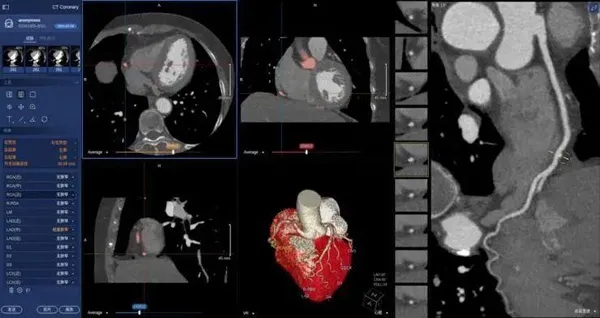

在醫(yī)學(xué)領(lǐng)域,機(jī)器視覺(jué)主要用于醫(yī)學(xué)輔助診斷。首先采集核磁共振、超聲波、激光、X射線、γ射線等對(duì)人體檢查記錄的圖像,再利用數(shù)字圖像處理技術(shù)、信息融合技術(shù)對(duì)這些醫(yī)學(xué)圖像進(jìn)行分析、描述和識(shí)別,最后得出相關(guān)信息,對(duì)輔助醫(yī)生診斷人體病源大小、形狀和異常,并進(jìn)行有效治療發(fā)揮了重要的作用。不同醫(yī)學(xué)影像設(shè)備得到的是不同特性的生物組織圖像,如X射線反映的是骨骼組織,核磁共振影像反映的是有機(jī)組織圖像,而醫(yī)生往往需要考慮骨骼有機(jī)組織的關(guān)系,因而需要利用數(shù)字圖像處理技術(shù)將兩種圖像適當(dāng)?shù)丿B加起來(lái),以便于醫(yī)學(xué)分析。